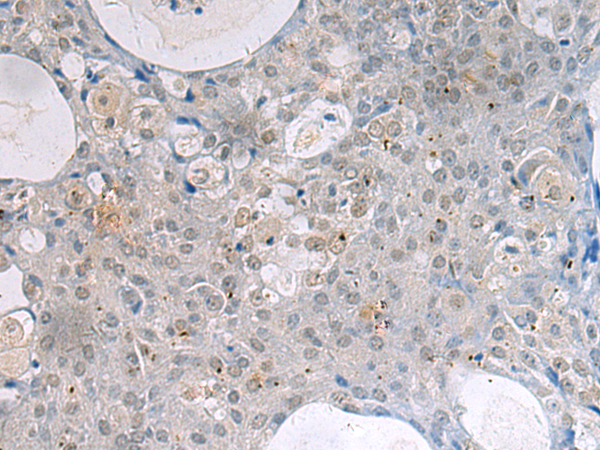

分类: 科研抗体货号: P12706别名: KHL4; DKELCHL应用: IHC反应种属: Human

分类: 科研抗体货号: P12738别名: G2L3应用: IHC反应种属: Human